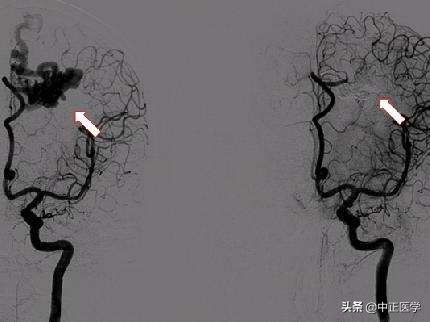

造影检查种类很多,可分为支气管造影、钡剂灌肠检查、口服胆囊造影、胃肠钡餐造影、静脉尿路造影、子宫输卵管造影、经皮肤穿刺胆道造影,心脏和动脉造影。造影检查是将一种比人体密度高或低的物质导入到人体内要检查的部位,人工地造成要检查部位密度差异,以构成对比,达到诊断的目的。